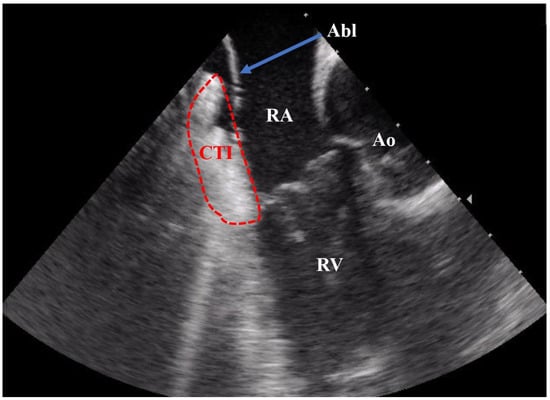

2.2. CTI Ablation Procedure